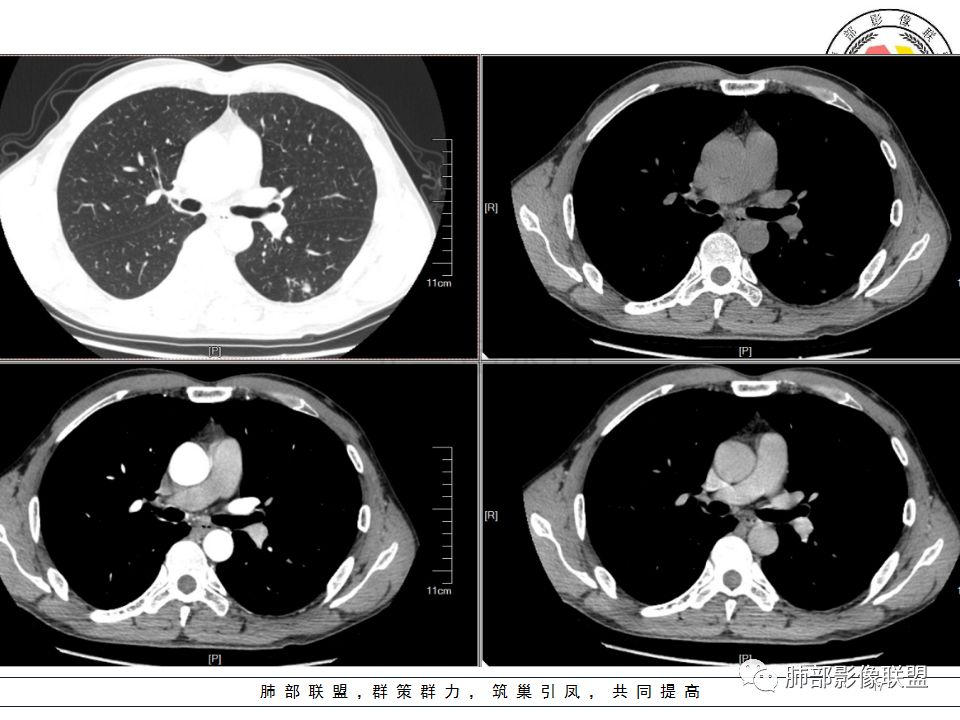

病历资料

左肺下叶背结节丶融合趋势,形态较单一,平直,无胸膜凹陷,目测轻强化,有支气管爬行丶子灶。诊断:TB>pC>腺癌。

左肺下叶结节,边缘平直为主,部分膨隆,卫星病灶,似乎无强化,糊墙,胸膜下脂肪间隙增宽,结核可能性大,腺癌待排。

左肺下叶背段孤立结节,长轴与胸膜平行,支气管近端截断,刀削平直,糊墙,卫星灶轻强化,考虑TB。

左肺下叶背段小结节 ,糊墙 ,胸膜外脂肪间隙增宽 ,引流支气管壁厚 ,有爬行征 ,病灶无明显强化,考虑结核可能。

考虑结核,左肺下叶病灶,强化不明显,胸膜反应性增厚,有卫星灶,强化不明显。

病史:男,50岁,胸痛15天,无抽烟;胸膜下病灶,有可能相关;

影像:病灶不规则,形态奇特,矢状位可能看到病灶的真实形态;上面近端病灶似乎与主病灶不相连续,多病灶?内侧似乎小花小草,疑为卫星灶;胸膜下病变,与胸膜关系不密切,胸膜线状强化;强化方式渐进性,感觉不均匀,也许是伪影;病灶凹陷平直不膨隆,考虑良性。诊断:结核;鉴别:腺癌(近胸膜端三个胸膜反应凹,偏上部层面毛刺不能除外,但其他地方没有,整体收缩力还比较弱,无钙化,考虑没有形成钙化和纤维化。

男性,胸疼,左肺下叶背段结节,边缘光滑,有平直收缩,轻度延迟强化?胸膜肥厚,有轻度胸膜牵拉,周围有卫星灶,考虑炎性病变,结核,隐球可能性大。鉴别腺癌。

左肺下叶背段结节,边缘较光整,平直,近端支气管未见明确截断征象,沿支气管走行,临近胸膜局限性增厚,增强目测未见明确强化,周围见稀疏小树芽分布,整体考虑良性病变,结核放前考虑。

男,50岁,左肺下叶结节影,似乎两个结节,相邻,上面一个偏内,有分叶,下面一个偏外,胸膜下,内侧有稍增厚的支气管影,并且支气管进入病灶内,周围有更小卫星灶,外侧有胸膜增厚,糊墙。总的来说,考虑炎性病灶,结核可能性最大。但靠内侧的结节有恶性特征,腺癌待排。

50岁男性,吸烟,胸痛15天。左肺下叶胸膜下结节,边缘平直为主,部分膨隆,但似乎呈山丘,沿支气管爬行,周围是卫星灶还是小花小草,考虑恶性,小细胞癌可能性大,结核待排。

左肺下叶背段结节,边缘光滑,有平直收缩,强化不明显,胸膜肥厚,有轻度胸膜牵拉,周围有卫星灶,考虑感染性病变,结核首选。

左肺下叶背段结节,形态近似两个结节融合或靠近,沿支气管走行分布,近侧支气管内见条状软组织,增强未见明确强化,周围见小树芽,首先考虑结核,鉴别小。

患者中年男性,因胸痛半月入院。查血常规、凝血功能、肾功能正常。有抽烟史。胸部CT:左肺下叶背段胸膜下与胸膜垂直长条形不规则病灶,支气管爬行改变,边缘欠清楚,部分层面呈葫芦样见血管集束征、周围点状卫星灶,增强无明显强化,左肺门淋巴结肿大。综合常规结核可能性大,其次小细胞肺癌。鉴别其他。

左肺下叶病变,边缘平直,似有U形凹陷,树芽及卫星病灶,支气管爬行征?无明显强化,考虑结核。

左肺下叶背段近胸膜下结节,部分边缘平直并可见卫星灶,增强后强化不明显,首先考虑结核。

中年男性,左肺下叶背段结节,内可见支气管充气征,周围有晕,周围有结节,局部胸膜增厚,可见脂肪间隙。考虑良性病变可能,隐球?,鉴别结核;病灶有沿支气管生长趋势,气道阻塞,经皮肺穿除外肺癌。

中年男性,胸痛,吸烟史。左肺下叶背段结节,边界清楚,局部见小毛刺及胸膜牵拉,部分层面成葫芦形,局部与胸膜宽基底相贴,邻近胸膜增厚。近端支气管达病灶边缘处,似略增厚。周围见少量卫星微结节及树丫。增强扫描无强化。考虑:1,结核:支持点有发病部位,邻近卫星灶及树丫,近病灶边缘支气管壁似略增厚,邻近胸膜增厚。不支持点,引流支气管壁增厚范围不够长。2,小细胞癌:支持点有局部葫芦形,似沿支气管向肺门区扩展。3,腺癌:支持点有毛刺和胸膜牵拉,当然结核也可以有这两个征象。不支持点有无强化。